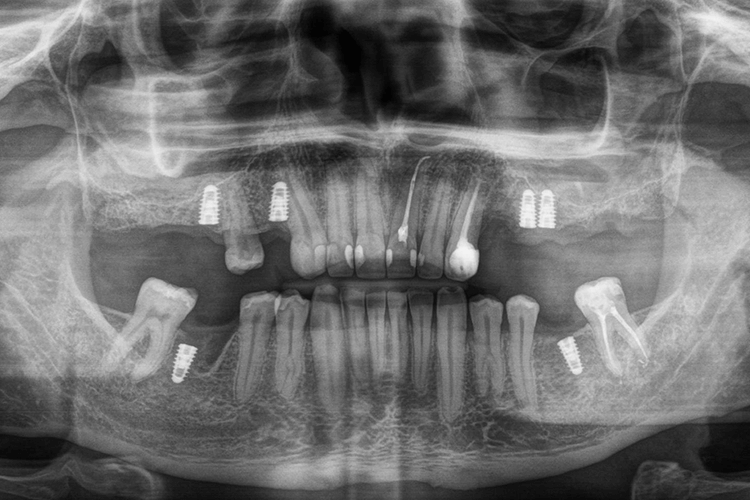

Во время проведения диагностики был обнаружен глубокий кариес фронтальных зубов, незначительная стертость фронтальных нижних зубов в связи с нарушением прикуса, а также отсутствовали нижние 6-е зубы с обеих сторон.

Корни зубов, которые ранее служили опорой для мостов на верхней челюсти, были разрушены и подлежали удалению, также в области этих зубов обнаружили кистогранулемы.